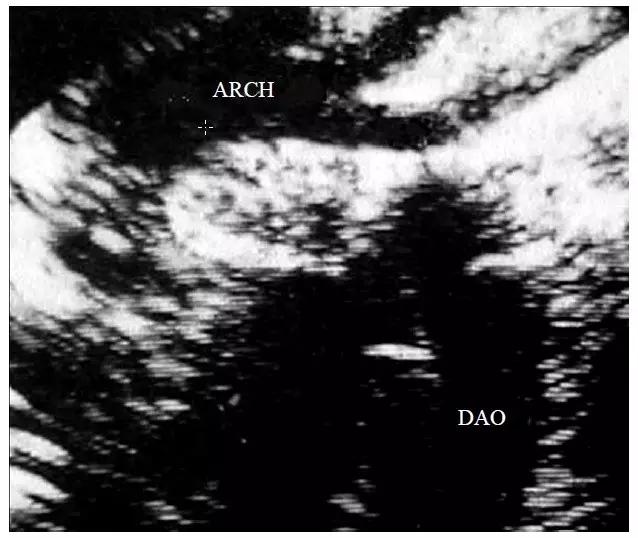

图10-6-2 A 型主动脉弓离断的二维超声心动图表现

图中显示胸骨上窝切面,主动脉弓左锁骨下动脉开口的远端离断(ARCH-主动脉弓 DAO-降主动脉)